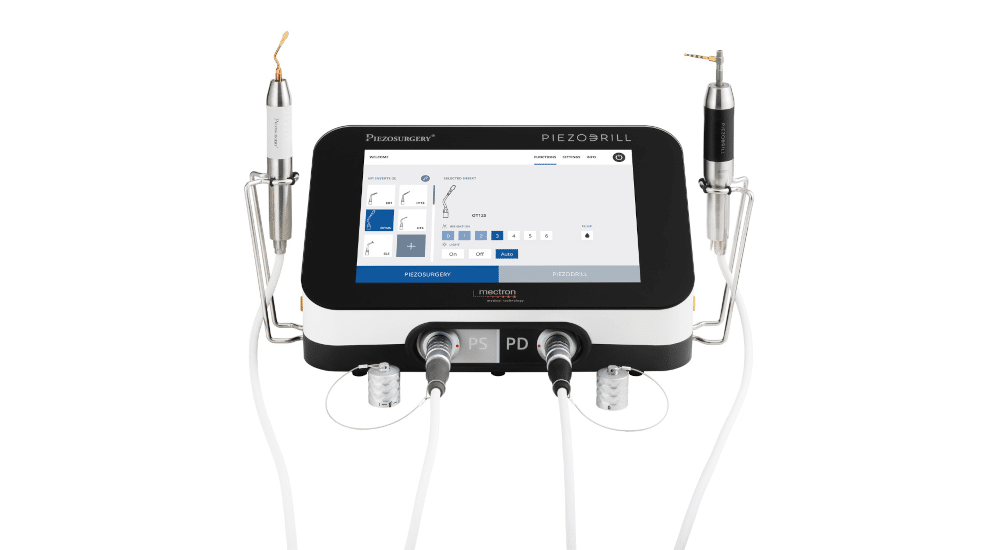

*Nouvelle approche de la chirurgie guidée : l’expertise par un logiciel de navigation 3D d’une planification sur modèle. Le projet planifié en amont sera transféré à l’image par un guide radiologique et analysé par le logiciel. Les rectifications d’axes décidées sur l’image seront facilement transposées en chirurgie par une modification du guide radiologique sur modèle. Ce guide permet un geste opératoire cadré et précis sans le stress inhérent aux actes effectués à main levée. Son coût est de 5 à 10 fois moindre que la majorité des autres systèmes.